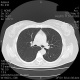

Выкладываю снимки. Заранее спасибо!

• https://radiomed.ru/sites/default/files/styles/case_slider_image/public/user/16468/110007.jpg?itok=1LORoCNi

• https://radiomed.ru/sites/default/files/styles/case_slider_image/public/user/16468/110008.jpg?itok=fijR7xvf

• https://radiomed.ru/sites/default/files/styles/case_slider_image/public/user/16468/110009.jpg?itok=OvL4IWKa

• https://radiomed.ru/sites/default/files/styles/case_slider_image/public/user/16468/110010.jpg?itok=CEZV99m1

• https://radiomed.ru/sites/default/files/styles/case_slider_image/public/user/16468/110011.jpg?itok=Dii8M3RL

• https://radiomed.ru/sites/default/files/styles/case_slider_image/public/user/16468/110012.jpg?itok=QSGdZfAJ

• https://radiomed.ru/sites/default/files/styles/case_slider_image/public/user/16468/110013.jpg?itok=vb2uxld2

• https://radiomed.ru/sites/default/files/styles/case_slider_image/public/user/16468/110014.jpg?itok=o-kA0Md5

• https://radiomed.ru/sites/default/files/styles/case_slider_image/public/user/16468/110015.jpg?itok=C7Llrcm0

• https://radiomed.ru/sites/default/files/styles/case_slider_image/public/user/16468/110016.jpg?itok=Qxx-nxR3

• https://radiomed.ru/sites/default/files/styles/case_slider_image/public/user/16468/110017.jpg?itok=9_l1RwkZ

• https://radiomed.ru/sites/default/files/styles/case_slider_image/public/user/16468/110018.jpg?itok=q79uMuJn

• https://radiomed.ru/sites/default/files/styles/case_slider_image/public/user/16468/110019.jpg?itok=YbsLfKaC

• https://radiomed.ru/sites/default/files/styles/case_slider_image/public/user/16468/110020.jpg?itok=Y_Z4JQAw

• https://radiomed.ru/sites/default/files/styles/case_slider_image/public/user/16468/110021.jpg?itok=I1mxUe7z

• https://radiomed.ru/sites/default/files/styles/case_slider_image/public/user/16468/110022.jpg?itok=1eVuVITL

• https://radiomed.ru/sites/default/files/styles/case_slider_image/public/user/16468/110023.jpg?itok=E6pNFr_x

• https://radiomed.ru/sites/default/files/styles/case_slider_image/public/user/16468/110024.jpg?itok=oB1Ygks0

• https://radiomed.ru/sites/default/files/styles/case_slider_image/public/user/16468/110025.jpg?itok=4D7HsHWk

• https://radiomed.ru/sites/default/files/styles/case_slider_image/public/user/16468/110026.jpg?itok=hbz--AUp

• https://radiomed.ru/sites/default/files/styles/case_slider_image/public/user/16468/110027.jpg?itok=sdNfMRNL

• https://radiomed.ru/sites/default/files/styles/case_slider_image/public/user/16468/110028.jpg?itok=UtDb8V_K

• https://radiomed.ru/sites/default/files/styles/case_slider_image/public/user/16468/110029.jpg?itok=S_chGBge

• https://radiomed.ru/sites/default/files/styles/case_slider_image/public/user/16468/110030.jpg?itok=Y982tsND

• https://radiomed.ru/sites/default/files/styles/case_slider_image/public/user/16468/110031.jpg?itok=W0bVVNyy

• https://radiomed.ru/sites/default/files/styles/case_slider_image/public/user/16468/110032.jpg?itok=_QxoM9MA

• https://radiomed.ru/sites/default/files/styles/case_slider_image/public/user/16468/110033.jpg?itok=37XcmArT

• https://radiomed.ru/sites/default/files/styles/case_slider_image/public/user/16468/110034.jpg?itok=kqGtOxAK

• https://radiomed.ru/sites/default/files/styles/case_slider_image/public/user/16468/110035.jpg?itok=5n9edlGJ

• https://radiomed.ru/sites/default/files/styles/case_slider_image/public/user/16468/110036.jpg?itok=EEP47s6p

• https://radiomed.ru/sites/default/files/styles/case_slider_image/public/user/16468/110037.jpg?itok=Klk8FkaC

• https://radiomed.ru/sites/default/files/styles/case_slider_image/public/user/16468/110038.jpg?itok=93-nf7Gu

• https://radiomed.ru/sites/default/files/styles/case_slider_image/public/user/16468/110039.jpg?itok=oVKmDJNC

• https://radiomed.ru/sites/default/files/styles/case_slider_image/public/user/16468/110040.jpg?itok=AcAEnnX4

• https://radiomed.ru/sites/default/files/styles/case_slider_image/public/user/16468/110041.jpg?itok=wTyC-KeE

• https://radiomed.ru/sites/default/files/styles/case_slider_image/public/user/16468/110042.jpg?itok=2VwAuplB

• https://radiomed.ru/sites/default/files/styles/case_slider_image/public/user/16468/110043.jpg?itok=vqi1LHLv

• https://radiomed.ru/sites/default/files/styles/case_slider_image/public/user/16468/110044.jpg?itok=K8rprK-c

• https://radiomed.ru/sites/default/files/styles/case_slider_image/public/user/16468/110045.jpg?itok=x_VcVTkd

• https://radiomed.ru/sites/default/files/styles/case_slider_image/public/user/16468/110046.jpg?itok=VWW-rR9a

• https://radiomed.ru/sites/default/files/styles/case_slider_image/public/user/16468/110047.jpg?itok=VTSFeBb0

спасибо Вам за ответы, не понимаю сама как так получилось, что не было видно снимков. теперь то их точно можно увидеть.